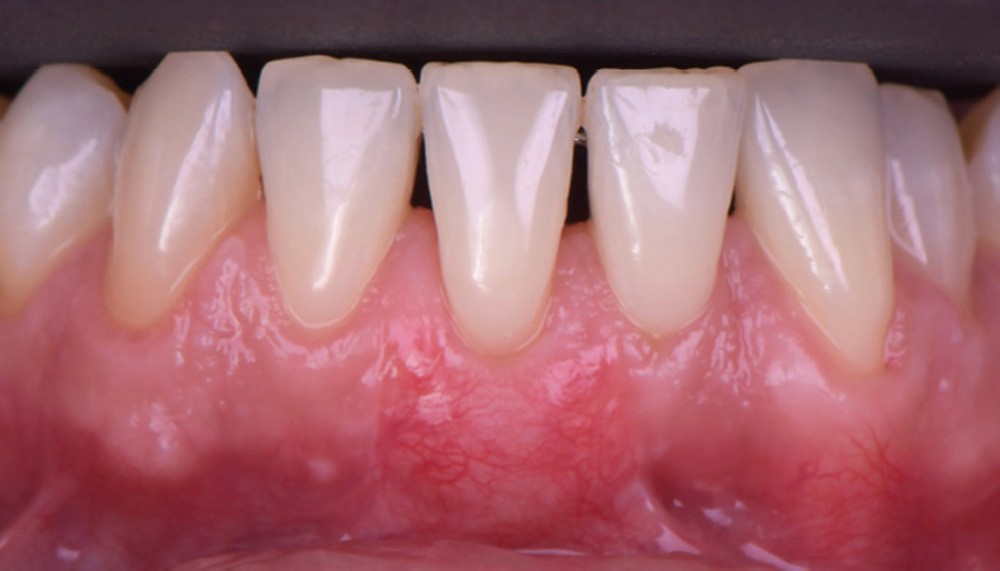

Le lambeau positionné coronairement associé à une greffe de conjonctif enfoui (fig. 1-4)

La stabilité du lambeau est primordiale dans la réussite de cette technique de recouvrement. En cas d’instabilité, même en l’absence d’erreurs techniques, l’analyse de certains facteurs liés au patient est indispensable. Afin de maintenir la stabilité du lambeau jusqu’à la dépose des points, le praticien doit veiller à l’adéquation du contrôle de plaque effectué par le patient, à l’absence de mastication impliquant la zone d’intervention, à la prévention de tout traumatisme ou de modifications des conditions locales par le patient.

Selon le Dr Sylvie Pereira, contrairement au maxillaire où la hauteur du lambeau déplacé coronairement est déterminée par la profondeur de la récession, à la mandibule, les incisions horizontales sont placées de manière à obtenir au moins 2 mm de tissu…